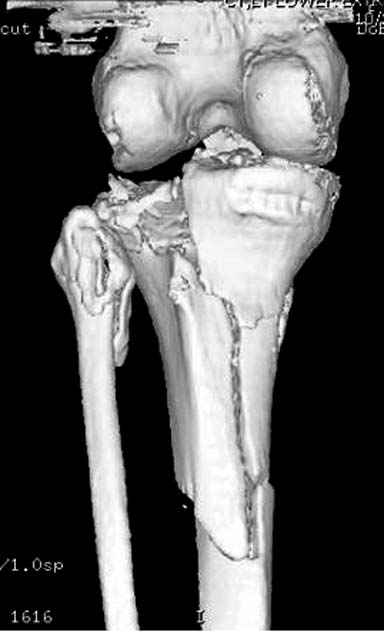

Отдельные переломы тибиал плато и перелом проксимальной трети большеберцовой кости отличаются от переломов тибиал плато с вовлечением диафиза. Здесь перелом тибиал плато типа Schatzker VI, полученный в результате высокоэнергетической травмы. Перелом метафиза образовал отрыв суставной поверхности от диафиза с вовлечением медиального и латерального мыщелков. Двухмыщелковые переломы из-за укрочения опасны развитием компартаментального синдрома, повреждением латерального мениска и связок.

Одна из проблем фиксации тибиал плато - это предупреждение мягкотканых осложнений, и это достигается проведением поэтапной фиксации. Такая тактика - первым этапом дистракция любым наружным фиксатором, а затем по готовности кожных покровов и после спадения отека операция. Операция в ранние сроки и без адекватной готовности кожных покровов лимитирует ваши действия опасностью осложнении, но без адекватного доступа фиксация получается ущербная. Для предупреждения осложнений лучше подождать и в зависимости от серьезности травмы можно ожидать иногда от 1 до 2 недель.

На вашем место я бы подождал с фиксацией до готовности кожных покровов, и за это время можно было подобрать соответствующий фиксатор, т.е более длинная пластина снаружи и медиальная пластина на апексе перелома как подпорка. Здесь приемлем как раз минимальный доступ.

Имеющаяся импрессия не потребовала пластики - достаточным оказалось поднять отломок

Если там действительная импрессия, пустое место без структуральных заполнителей, кость или синтетические материалы, не восстановится, а образуется коллапс, и ось конечности поведет после нагрузки. Кроме того там возможно "болт стяжка"?, в медиальной стороне выступает за кортекс, можно было укоротить! Потом создается впечатление, что не соответствуют мыщелки большеберцовой и бедренной костей? Покажите снимок.